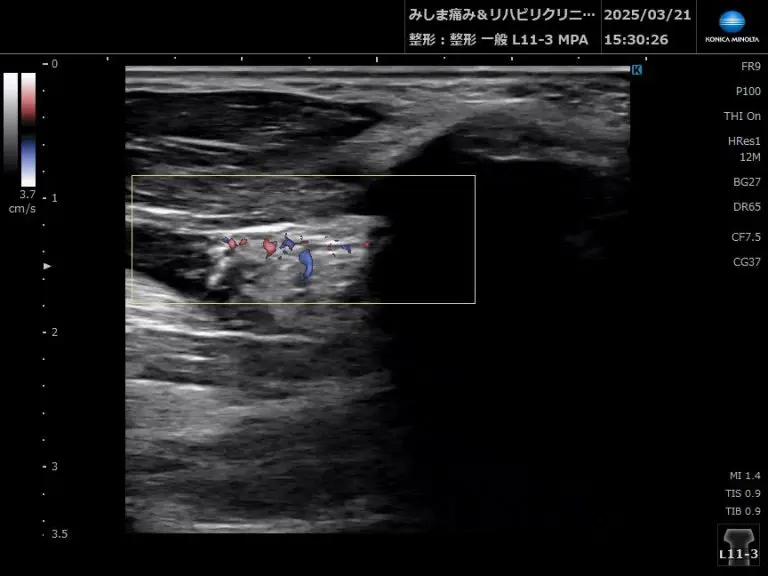

- 滑膜肥厚・滑膜炎の評価

→ リウマチ性疾患などで滑膜が肥厚。ドプラーモードで血流評価も可能。

- 炎症の有無をチェック